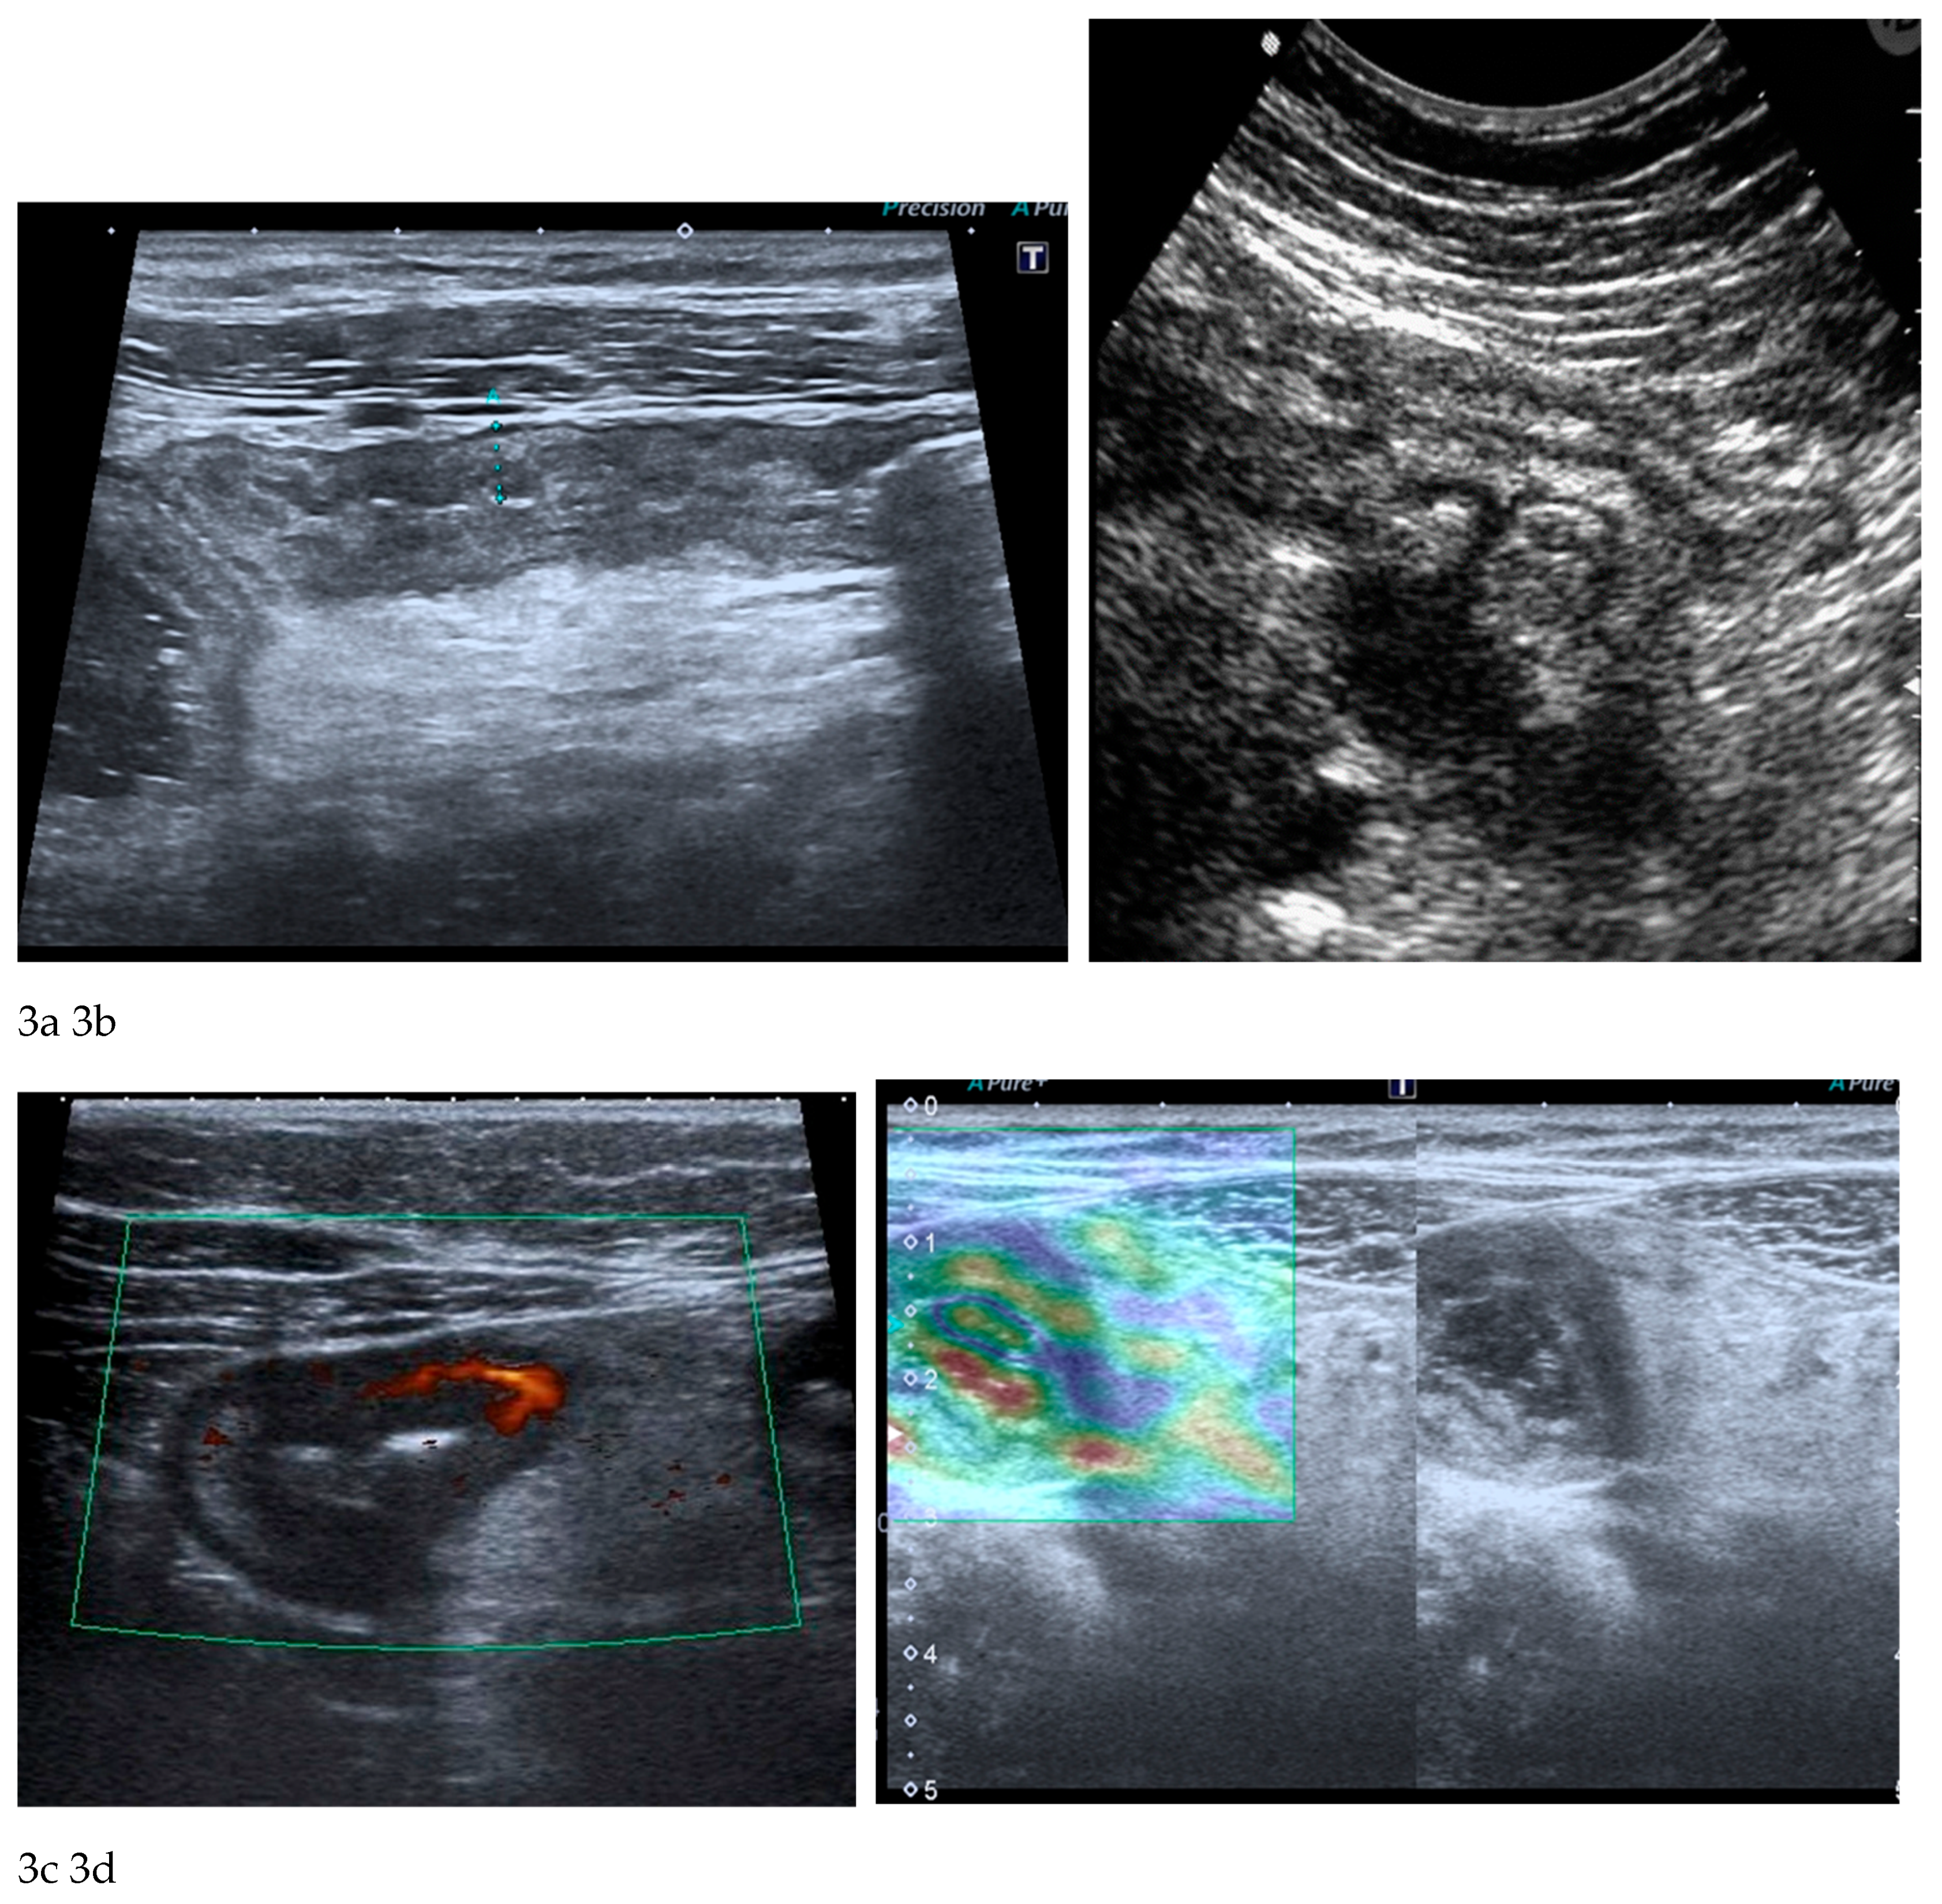

The fundamental strengths of IUS derive from its ability to visualize bowel wall thickness, mural stratification, and peristaltic activity with high temporal resolution. Bowel wall thickening represents one of the most robust markers of inflammatory activity and, when combined with colour or power Doppler evaluation, ultrasound becomes a sensitive tool for assessing mural hypervascularization, considered a surrogate marker of active inflammation [

23,

24,

25,

26] (

Figure 3a-c). Contrast-enhanced ultrasound (CEUS) allows dynamic evaluation of microvascular perfusion, enabling a more refined analysis of transmural enhancement patterns. CEUS is useful for early assessment of therapeutic response as well as for the identification and characterization of abscesses. Another promising development is ultrasound elastography, which may be useful in distinguishing inflammatory from fibrotic strictures, a diagnostic challenge traditionally dominated by MRE [

25] (

Figure 3d).